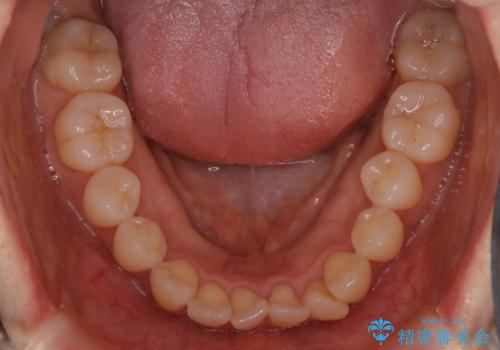

- 前歯のがたつきが気になるとご相談にいらした患者様です。矯正検査の結果、骨格的なズレが大きかったため当初の治療計画では外科矯正をご案内しました。ご本人が手術を望んでおらず、可能な限りの改善を目指すことを目標に治療を開始しました。

元々の骨格的なズレが大きかったため、当初は外科矯正をご提案していました。患者様の強いご希望により、非外科的な処置のみで可及的な改善を目指すことを目標に治療を行いました。以前よりもしっかり噛めるようになり、見た目も劇的に改善したことで大変ご満足いただけました。